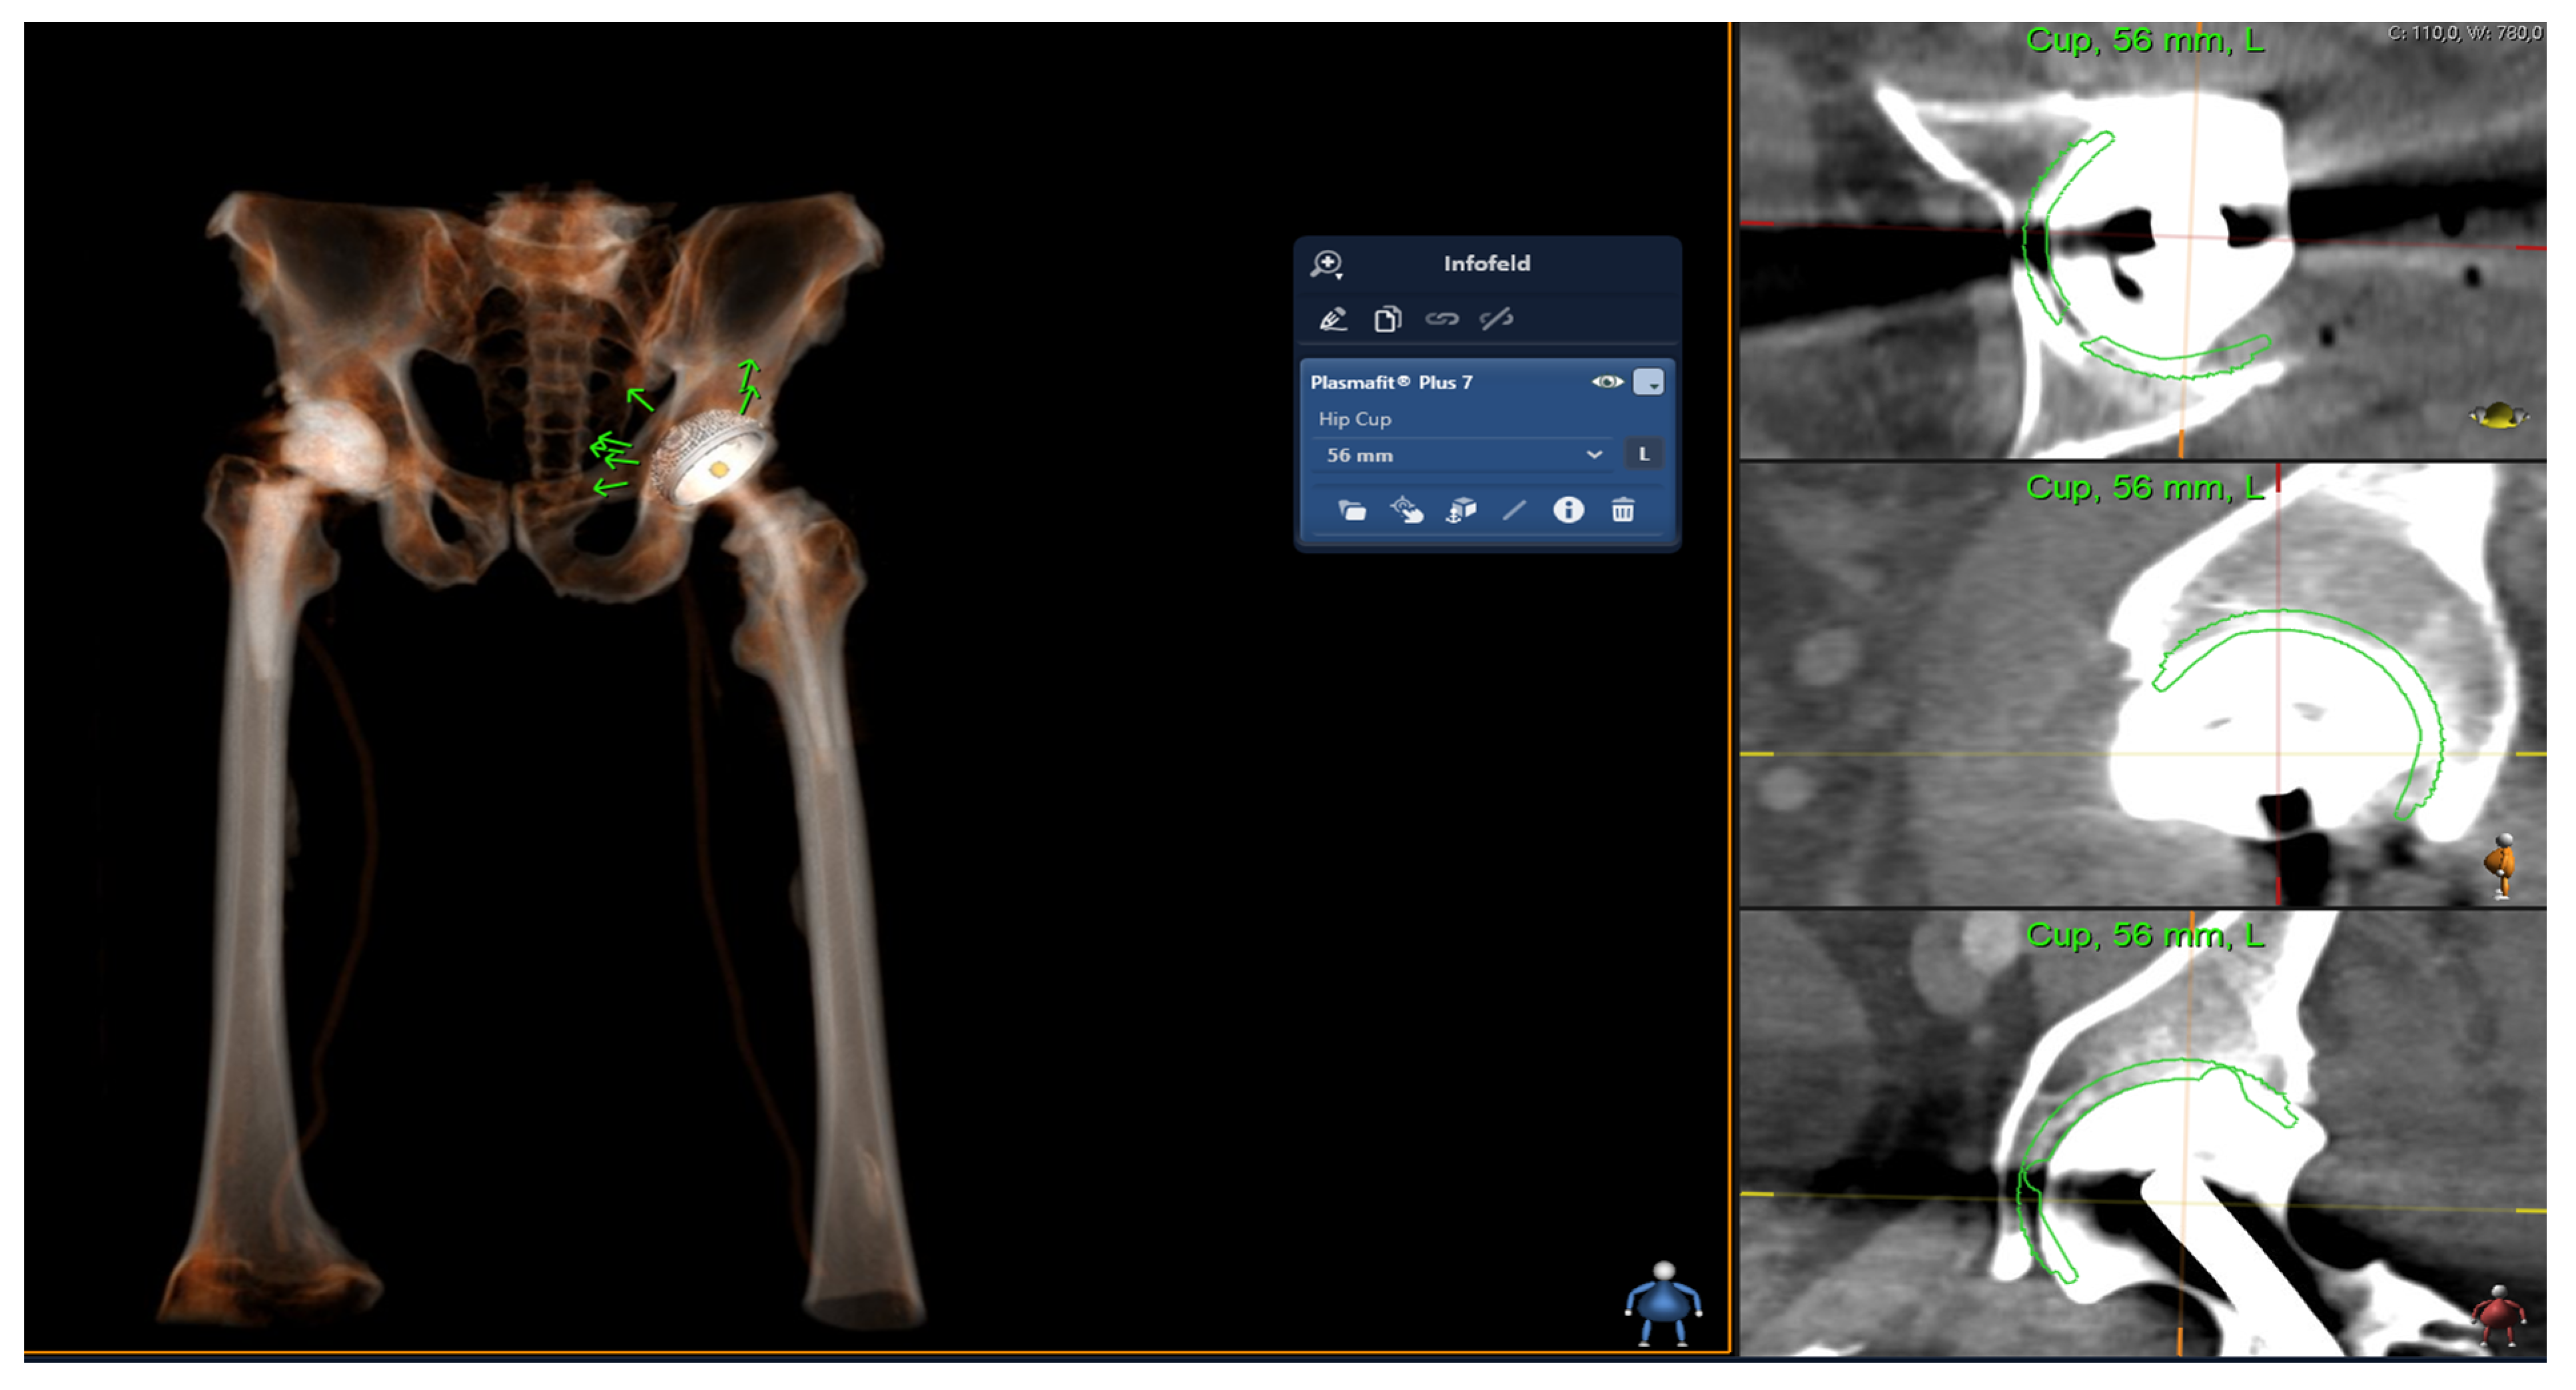

2.2. Digital Templating

Aesculap Plasmafit